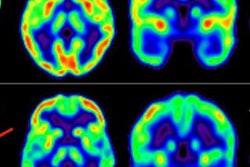

Predicting how multiple sclerosis will progress can be tricky, and biomarkers are needed that can help to distinguish between patients who will show rapid disability accumulation and those who will remain stable. A German group has used MRI to investigate the effectiveness of these biomarkers.